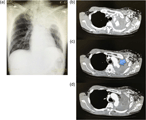

An unusual case of massive hematemesis caused by aorto-esophageal fistula due to mycotic aneurysm of mid-thoracic aorta in a patient without prior aortic instrumentation

Erion Qaja and others

Journal of Surgical Case Reports, Volume 2017, Issue 5, May 2017, rjx084, https://doi.org/10.1093/jscr/rjx084